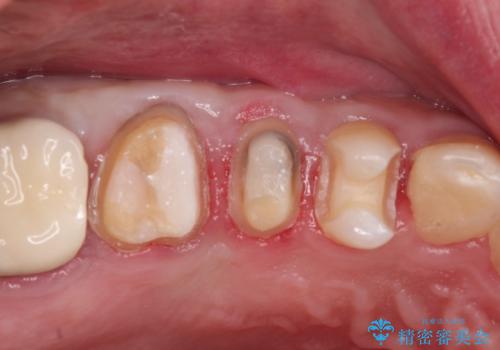

- 定期検診にて不良補綴物、及び虫歯を認めオールセラミッククラウンにて治療を行いました。

右上第二小臼歯はカリエス除去中に露髄を認め、部分的断髄法にて歯髄を保存しております。